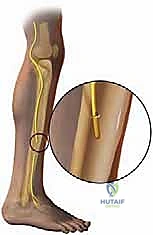

- The Superficial Peroneal Nerve (SPN):

- Course: Emerging from the common peroneal nerve, it descends in the lateral compartment of the leg, superficial to the peroneal muscles (peroneus longus and brevis). Approximately two-thirds down the leg, it pierces the deep fascia to become superficial. It then courses anterior to the fibula, dividing into its terminal branches (medial dorsal cutaneous nerve and intermediate dorsal cutaneous nerve) which innervate the dorsum of the foot.

- Risk: Highly vulnerable during ankle fracture ORIF (especially lateral approaches), arthroscopic ankle lateral portal placement, and any lateral midfoot surgery.

- Specific Branch Risk: Its terminal medial branch, the dorsomedial cutaneous nerve, is particularly at risk with bunionectomy along the dorsomedial hallux.

* Clinical Pearl: This nerve is often adherent to muscle and fascia after severe stretch injury, as seen in this classic image (FIG 2). This adherence can make dissection challenging and increase the risk of iatrogenic injury if not approached meticulously.